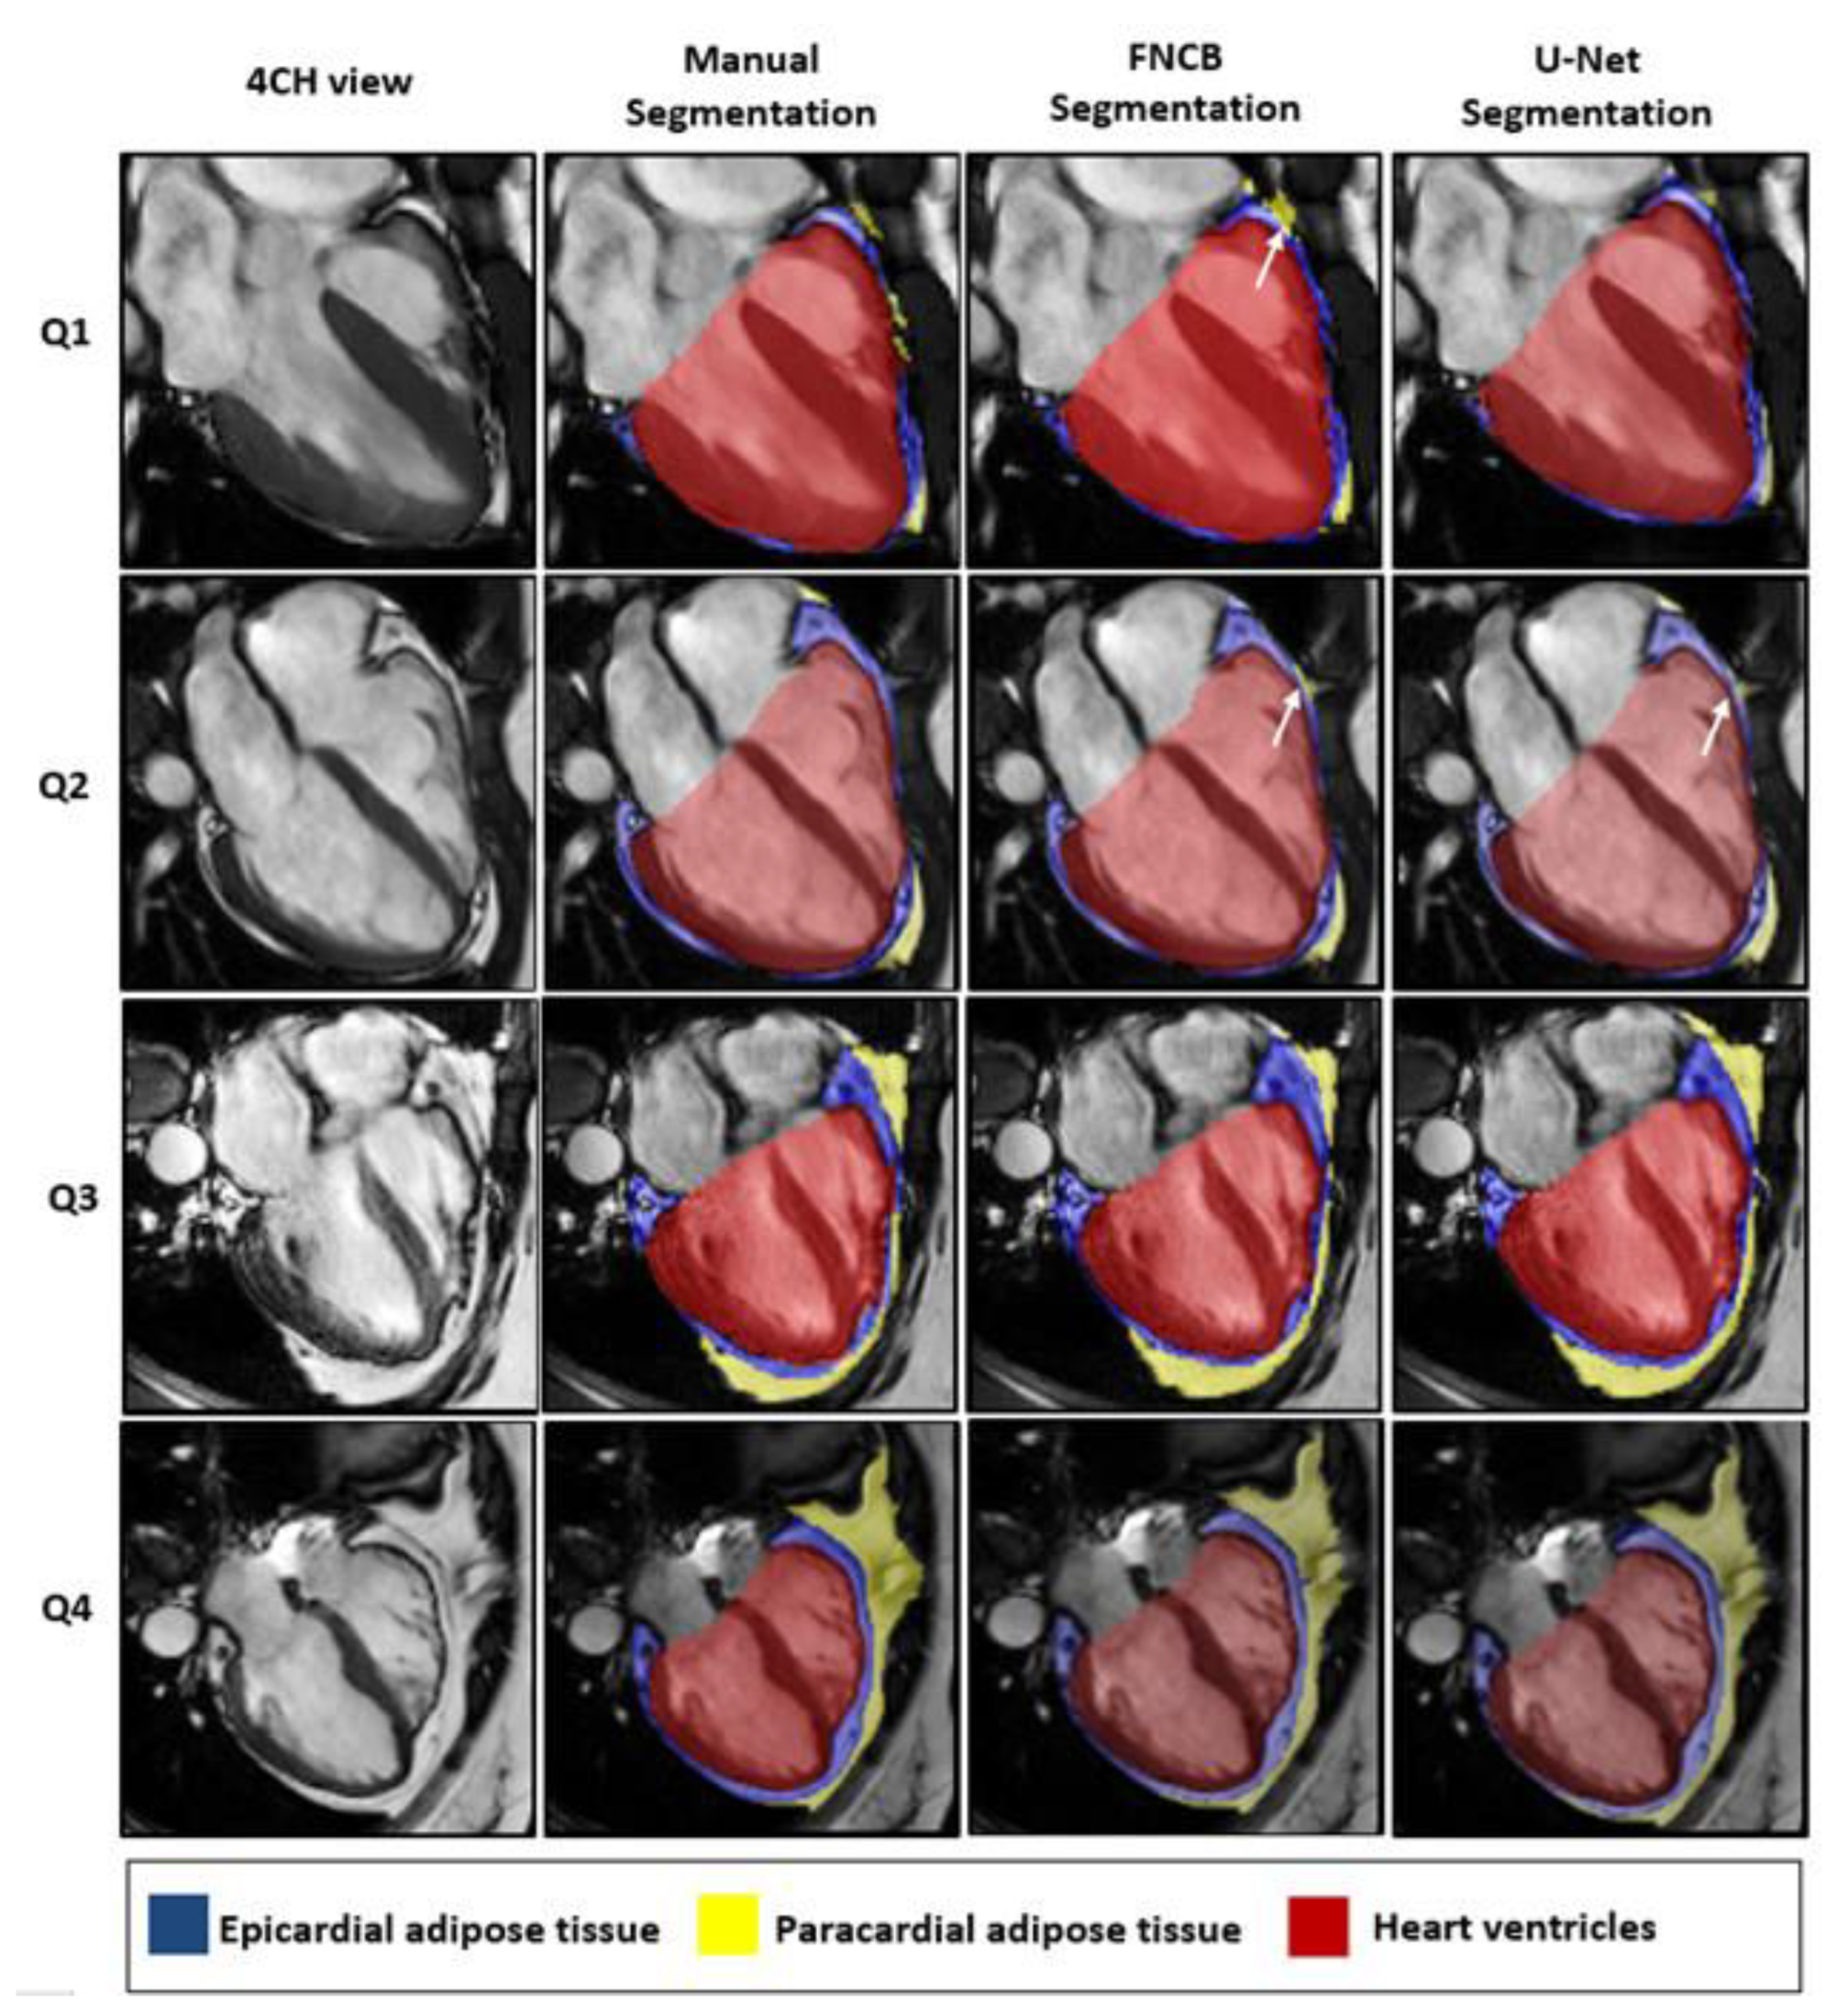

4.5. Performances across Quartiles